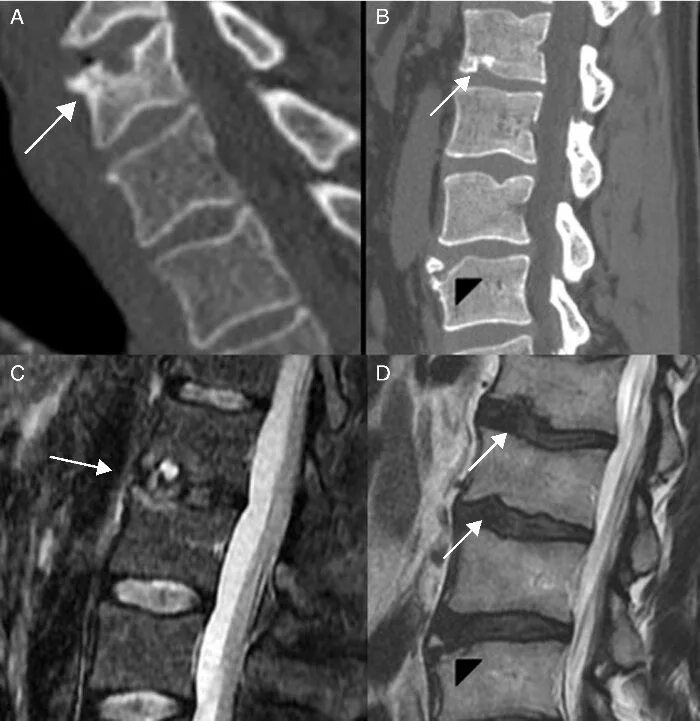

Что значит грыжа шморля